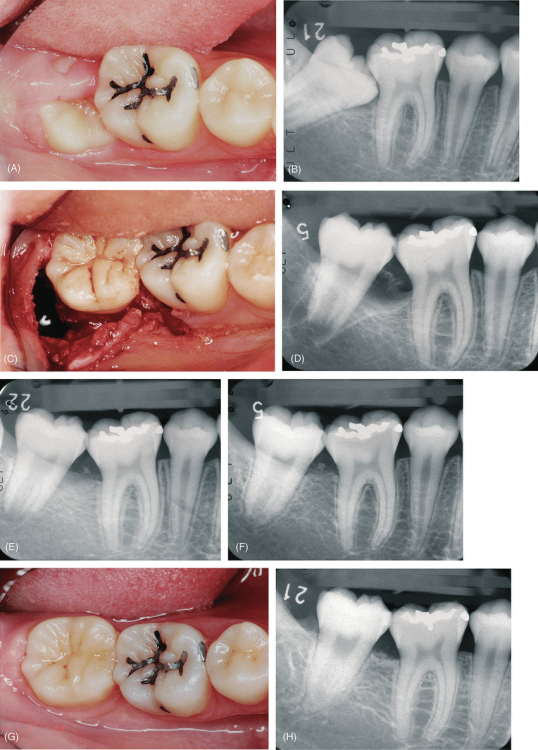

Dr.Deletle Опубликовано 22 июля, 2023 Поделиться Опубликовано 22 июля, 2023 (изменено) Этот кейс интересен тем, что у пересаживаемого 2.8 полностью сформированы корни. Пациент Н., 35лет, зуб 3.6 подлежит удалению по терапевтическим показаниям. Донором был выбран зуб 2.8. Фото №1, 2 - ситуация ДО на фото и срезе КЛКТ Фото №3 - планирование на реконструкции ОПТГ из КЛКТ Фото №4 - шаблон зуба 2.8 Фото №5, 6 - операция, удален 3.6, припасован шаблон, пересажен 2.8 (фиксирован швами и шиной к 3.7) Фото №7 - КТ сразу после пересадки Фото №8, 9 - депульпирование пересаженного 2.8 через 2 недели Фото №10 - снятие шины через 2нед после пересадки Фото № 11, 12, 13 - состояние в полости рта и на срезе КТ через год после пересадки, видно сформированное периодонтальное пространство, здоровая костная ткань, жалоб у пациента нет, полноценно жует как обычным зубом Изменено 22 июля, 2023 пользователем Dr.Deletle 4 3 Ссылка на комментарий

Dr.Deletle Опубликовано 23 июля, 2023 Автор Поделиться Опубликовано 23 июля, 2023 @annda т.к. удаляется нерв и ниже процент приживаемости и восстановления периодонта Ссылка на комментарий

Irouil Опубликовано 23 июля, 2023 Поделиться Опубликовано 23 июля, 2023 @Dr.Deletle а как влияет пульпа на сохранность периодонта? Насколько я знаю, основные факторы там внераневое время, отсутствие костно-цементного контакта при иммобилизации и время иммобилизации. Ссылка на комментарий

annda Опубликовано 23 июля, 2023 Поделиться Опубликовано 23 июля, 2023 2 часа назад, Dr.Deletle сказал: @annda т.к. удаляется нерв и ниже процент приживаемости и восстановления периодонта Как на связку пульпа влияет ,не понимаю:( Если делаем аутотрансплантацию взрослому,эндо в любом случае делаем,тут нет вариантов.Или я чего-то не знаю? Ссылка на комментарий

АнтонТЛТ Опубликовано 23 июля, 2023 Поделиться Опубликовано 23 июля, 2023 2 часа назад, annda сказал: Как на связку пульпа влияет ,не понимаю:( Если делаем аутотрансплантацию взрослому,эндо в любом случае делаем,тут нет вариантов.Или я чего-то не знаю? Если апекс не сформирован, то возможно пульпа может оживится при трансплантации 1 Ссылка на комментарий

Dr.Deletle Опубликовано 23 июля, 2023 Автор Поделиться Опубликовано 23 июля, 2023 (изменено) @Irouil я и не писала, что пульпа влияет на сохранность периодонта) А депульпируем здесь обязательно, чтобы не было воспалительных изменений в периодонте и воспалительной резорбции Изменено 23 июля, 2023 пользователем Dr.Deletle Ссылка на комментарий